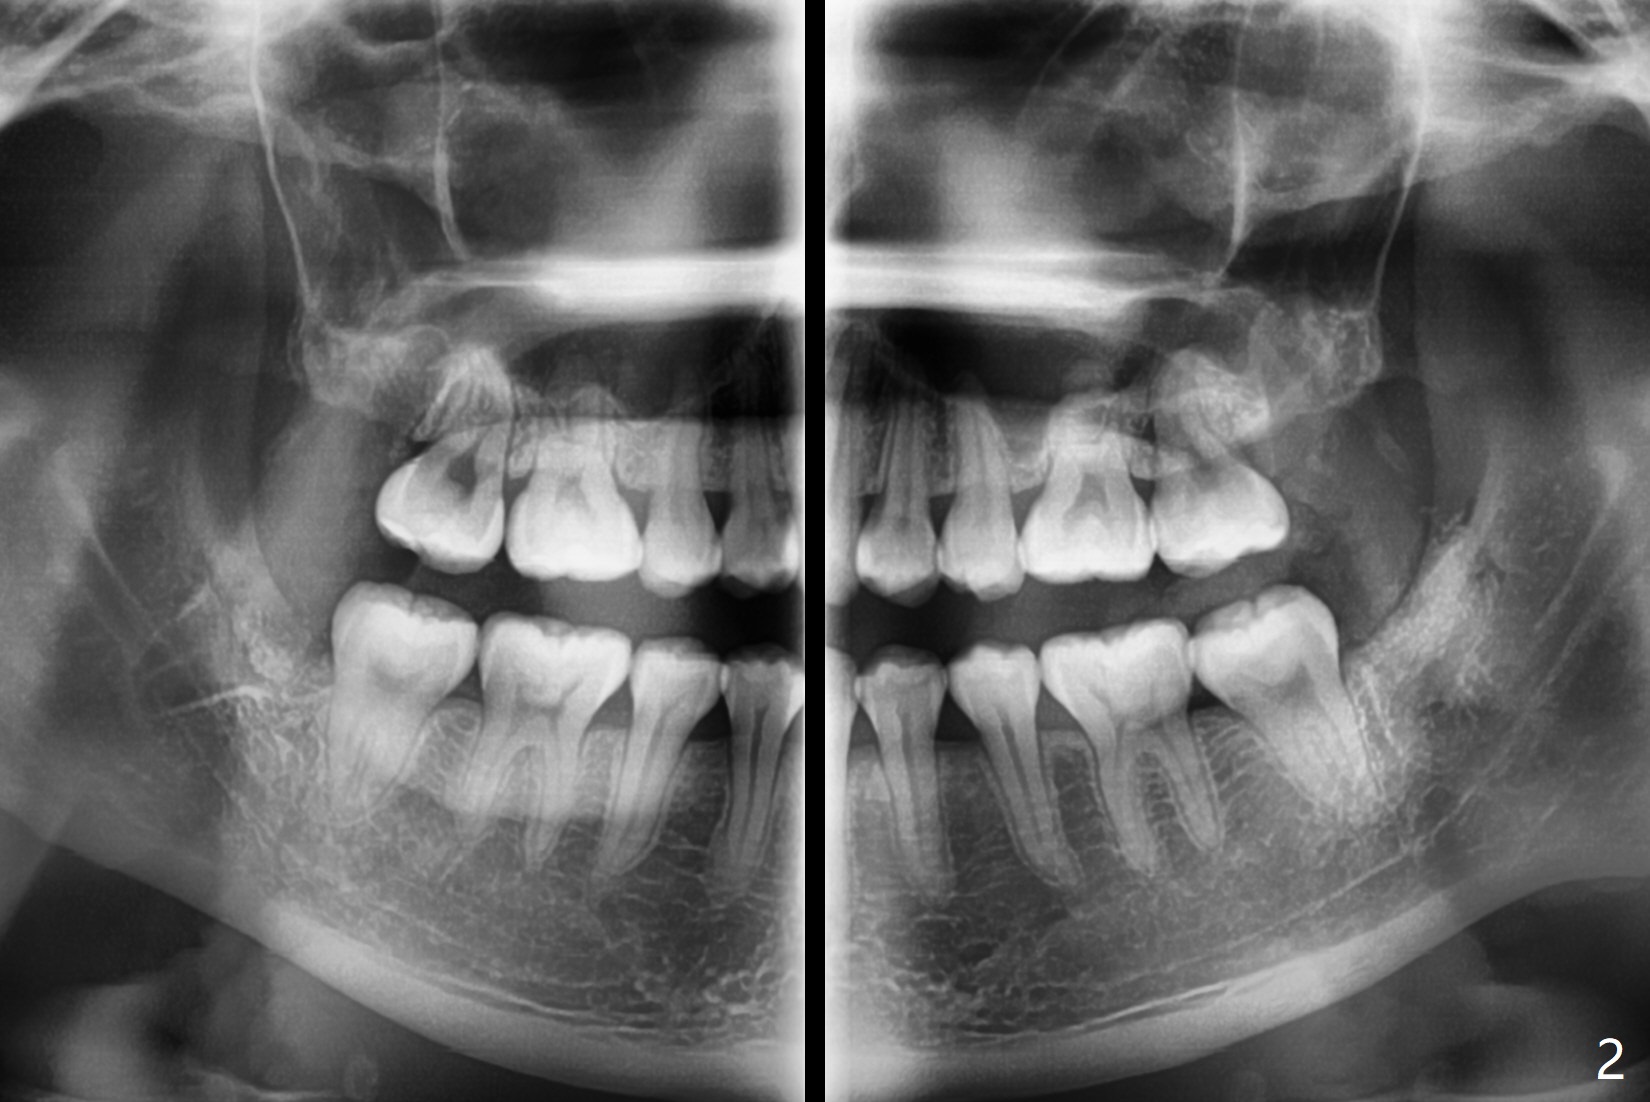

22岁女要求拔除4个智齿,右下接近下齿槽神经,必要时拍摄局部CT,如果牙根跨越神经,劈根取出,新拍摄全景片显示根尖与神经关系不是那么密切。牙槽窝底部放置底部沾有PRF液体的(结果没有这样做,因为抽血很少)Osteogen plug(一种胶原骨塞,结果放胶原塞1/2),牙槽窝近中,第二磨牙远中放置粘性骨粉,牙槽窝上部放置PRF膜(结果放胶原塞另外1/2,抽血困难),PGA缝线。左下牙槽窝放置沾有PRF液体(结果没有这样做,因为抽血很少)的胶原塞(第二磨牙远中没有缺损),覆盖PRF膜(很小一块,以及一半胶原塞),缝合。